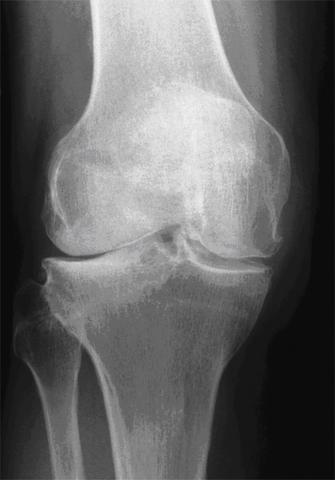

Nach einem Riss des vorderen Kreuzbands ist eine mehrmonatige Rehabilitation wichtig. Knarren Schnappen oder Knacksen des Kniegelenks während der Beugung Schmerzen bei Belastung besonders an der Innen- oder Rückseite der Kniescheibe Patella Blockadegefühl bei der Streckbewegung Steifes Knie nach langem Sitzen Nach einer Operation am Kniegelenk kann es trotz erfolgreicher Operation immer wieder zu. Immernoch Probleme nach Kreuzband OP.

Die Schmerzen können aufgrund mehrerer Umstände auftreten die auf jede Knieoperation zutreffen. Der Kreuzbandriss gehört zu den häufigsten Knieverletzungen bei Hobbysportlern. Hallo zusammen Im November habe ich mir mein vorderes Kreuzband und den Außenmeniskus im linken Knie gerissen.